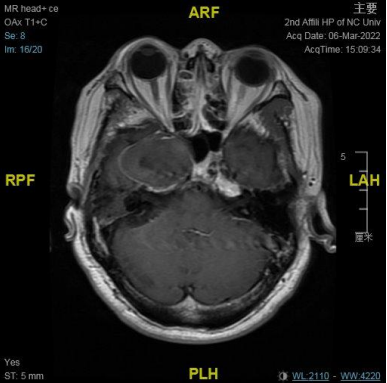

右侧中颅窝鞍旁见一大小约 34 mm✕40 mm✕47 mm 肿块,信号混杂,T1、T2 均呈等低高混杂信号,DWI 呈不均匀混杂信号,边缘包膜呈稍长 T1 短 T2 信号,肿块边界清;肿块无强化,边缘包膜呈明显强化。

结合此病例影像学特点:T1、T2 均呈等低高混杂信号,肿块边界清;肿块无强化,边缘包膜呈明显强化。

从 MRI 增强扫描上肿块无强化,可与神经鞘膜瘤相鉴别;CTA 成像无强化环及强化结节表现,肿块将颈内动脉向后推挤,MRI 增强也无病变周边高信号环及典型的动脉搏动伪影表现,这些影像学表现上可与动脉瘤相鉴别。